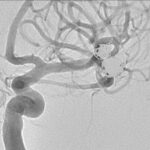

Fig. 4. Angiografia digital 3D: Aneurisma sacular pequeño bilobulado, con pseudoaneurisma asociado, responsable del sangrado.

Fig. 6. Angiografia digital con substracción: Oclusión de aneurisma sacular pequeño bilobulado, a nivel de la bifurcación de la arteria cerebral media izquierda, con cast de coils estable.